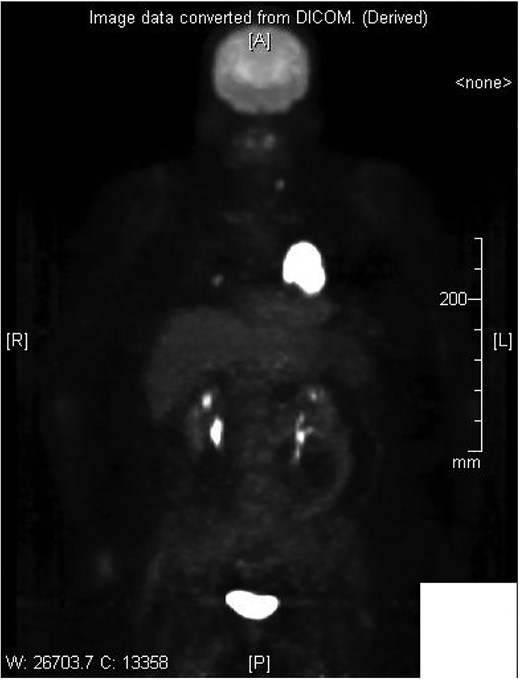

Cardiothoracic surgery team was consulted, and the patient underwent a pericardial window with 750 cc of serosanguinous fluid drained from her pericardial space. A chest tube placed status-post pericardial window, which initially continued to drain 500 cc of serosanguinous fluid, with fluid volume decreasing in the following 5 days with stable vital signs. The patient tolerated the switch to p.o. amiodarone and discharged upon her request to restart chemotherapy, after removal of her chest tube. Histopathology results of the pericardial fluid were positive for reactive mesothelial cells and chronic inflammation. Follow-up positron emission tomography (PET)/CT scan depicted increased uptake in the cardiac chamber (Fig. 4). Repeated echocardiography 2 months later depicted a return in pericardial fluid with the patient remaining hemodynamically stable with preserved ejection fraction.

DISCUSSION